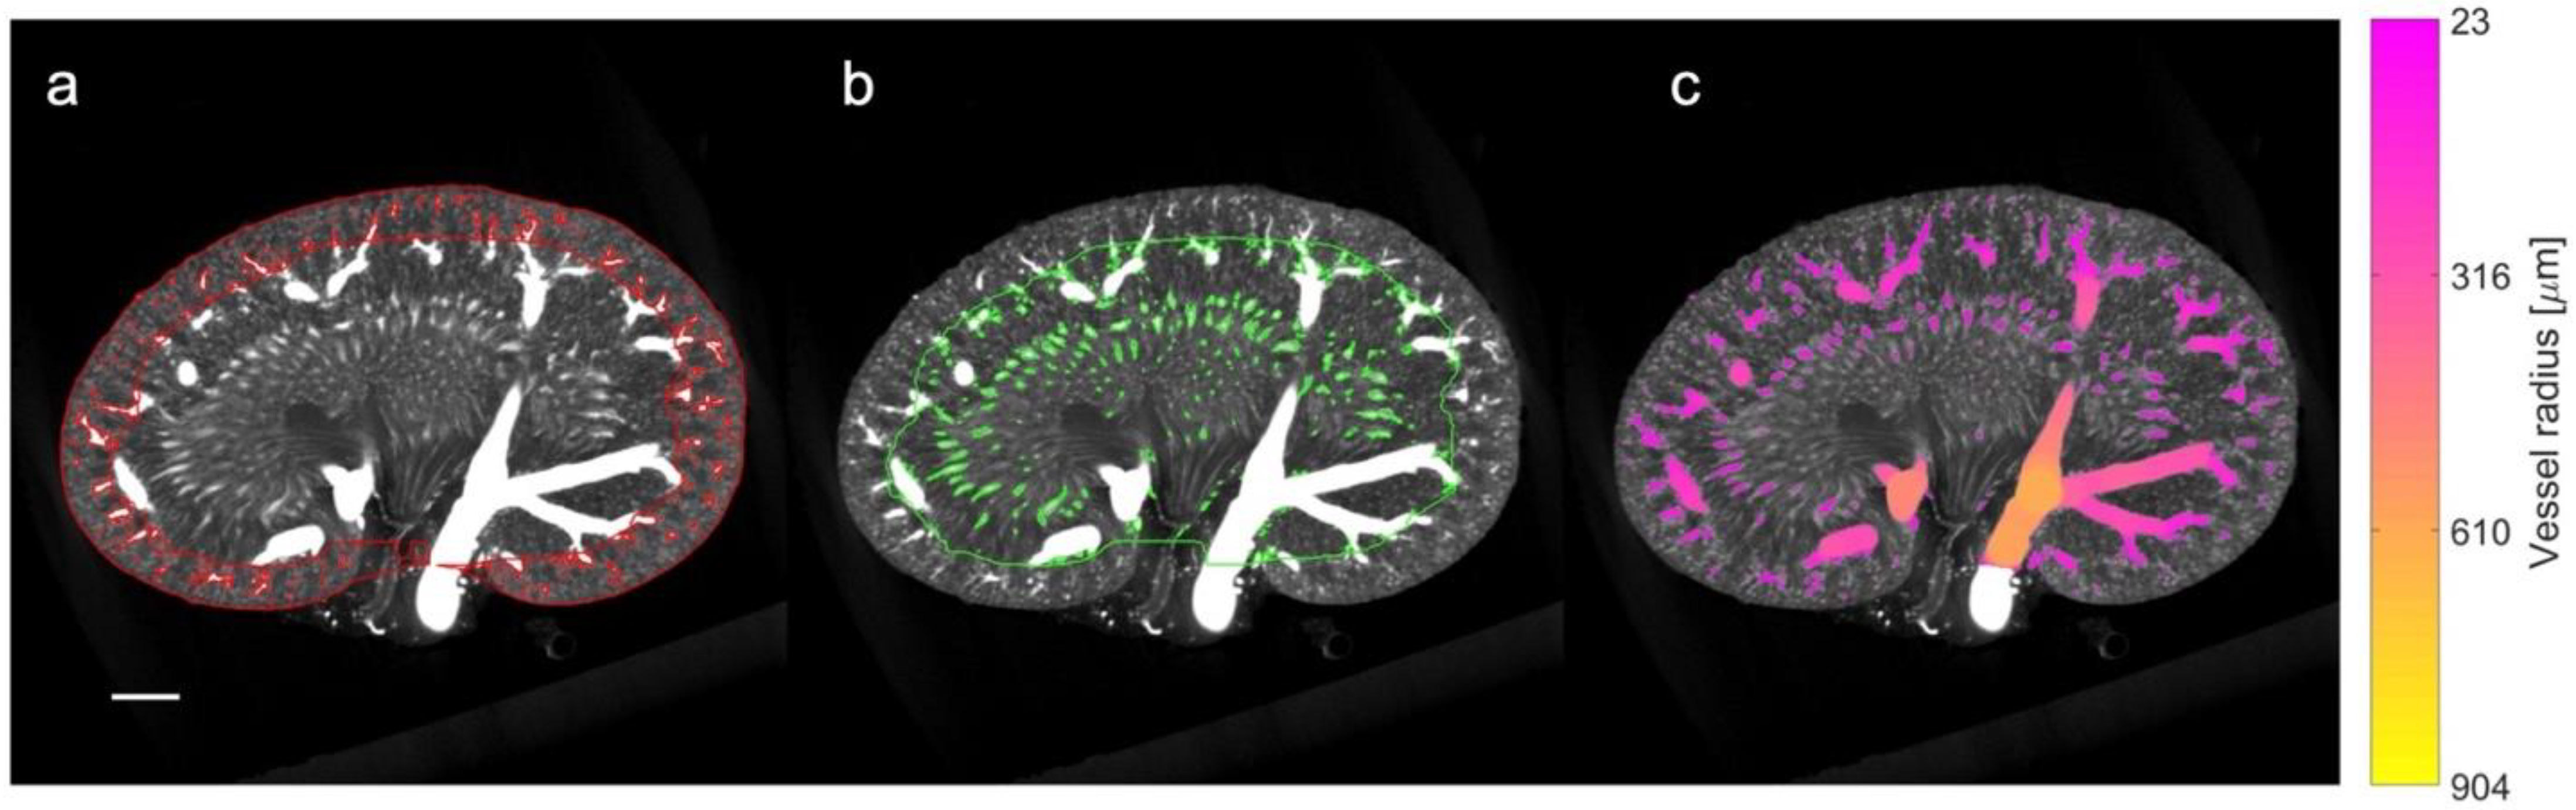

2.5. Ex Vivo µCT Imaging

2.6. Kidney Histology

2.9. µCT Processing and Quantification of Vascular Density

3.4. Qualitative and Quantitative Assessment in µCT

- Andersen, S.B.; Taghavi, I.; Kjer, H.M.; Søgaard, S.B.; Gundlach, C.; Dahl, V.A.; Nielsen, M.B.; Dahl, A.B.; Jensen, J.A.; Sørensen, C.M. Evaluation of 2D Super-Resolution Ultrasound Imaging of the Rat Renal Vasculature Using Ex Vivo Micro-Computed Tomography. Sci. Rep. 2021, 11, 24335. [Google Scholar] [CrossRef] [PubMed]